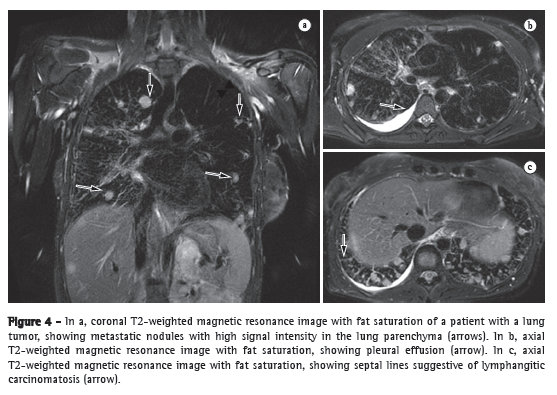

After the presence of PH and its correct hemodynamic classification are confirmed by RHC, various tests should be performed in order to determine the specific etiology of PH. It should be highlighted that idiopathic PH is a differential diagnosis, and it is fundamental to follow an appropriate flowchart to facilitate the diagnostic investigation (Figure 4).